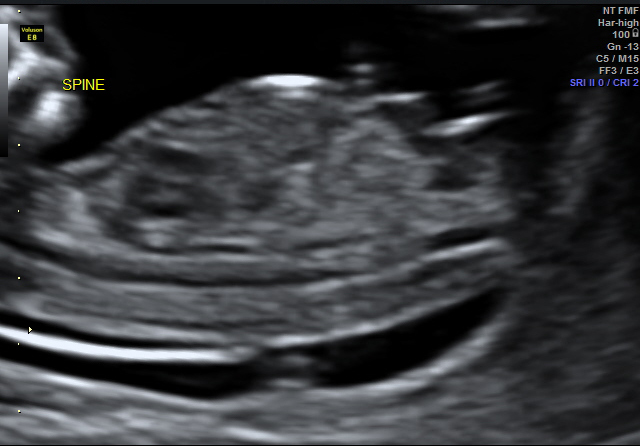

I don't have a complete shot head to toe of baby with nub exposed but I do have a close up... All guesses appreciated!